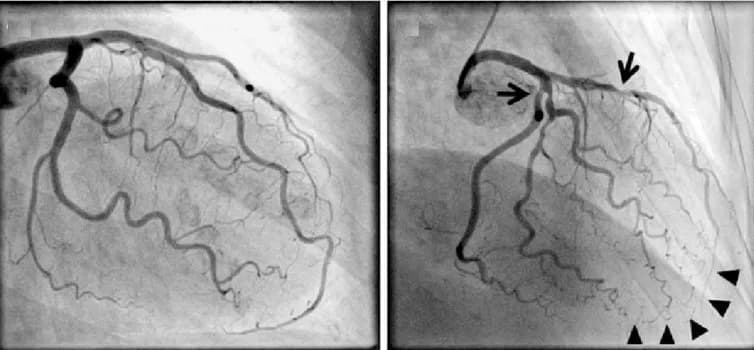

Mảng xơ vữa không ổn định: Loại mảng bám này có sự tăng trưởng không liên tục và không đều, bao gồm một lõi lớn chứa nhiều chất béo giàu cholesterol (LDL), lẫn với các tế bào miễn dịch và các yếu tố mô. Lõi này được bao bọc bởi một lớp sợi mỏng (50-65 mcm) có dấu hiệu xói mòn và sẹo. Khi chụp động mạch, mảng bám này có thể chỉ biểu hiện bằng hẹp trung bình (≤ 50%) và không hạn chế dòng chảy phía hạ lưu, vì nó có xu hướng phình ra ngoài và không đi vào trong lòng động mạch. Nguy cơ của mảng bám này phụ thuộc vào hoạt động viêm và tính nhạy cảm của nó đối với sự vỡ, chứ không phụ thuộc vào mức độ hẹp mà nó gây ra. Mảng xơ vữa không ổn định có thể được phát hiện bằng phương pháp chụp động mạch vành. Loại mảng bám này ít gây hẹp nặng (<60%), do đó không ảnh hưởng nhiều đến việc cung cấp oxy (DO2). Đau thắt ngực thường hiếm gặp, và chụp động mạch có thể cho thấy hẹp không đáng kể, thậm chí test gắng sức cũng có thể âm tính. Tuy nhiên, mảng bám này có thể bị mất ổn định, vỡ ra và gây huyết khối trong động mạch, dẫn đến thiếu máu cục bộ. Điều này có thể dẫn đến nhồi máu với sóng Q và ST chênh lên (STEMI). Mảng bám không ổn định chịu trách nhiệm cho 40-50% các trường hợp nhồi máu sau phẫu thuật (thường xảy ra trong vòng 36 giờ sau phẫu thuật). Điều trị dự phòng tập trung vào việc sử dụng thuốc chống tiểu cầu và statin để ổn định mảng bám và ngăn ngừa huyết khối [tham khảo: AHA Journals].